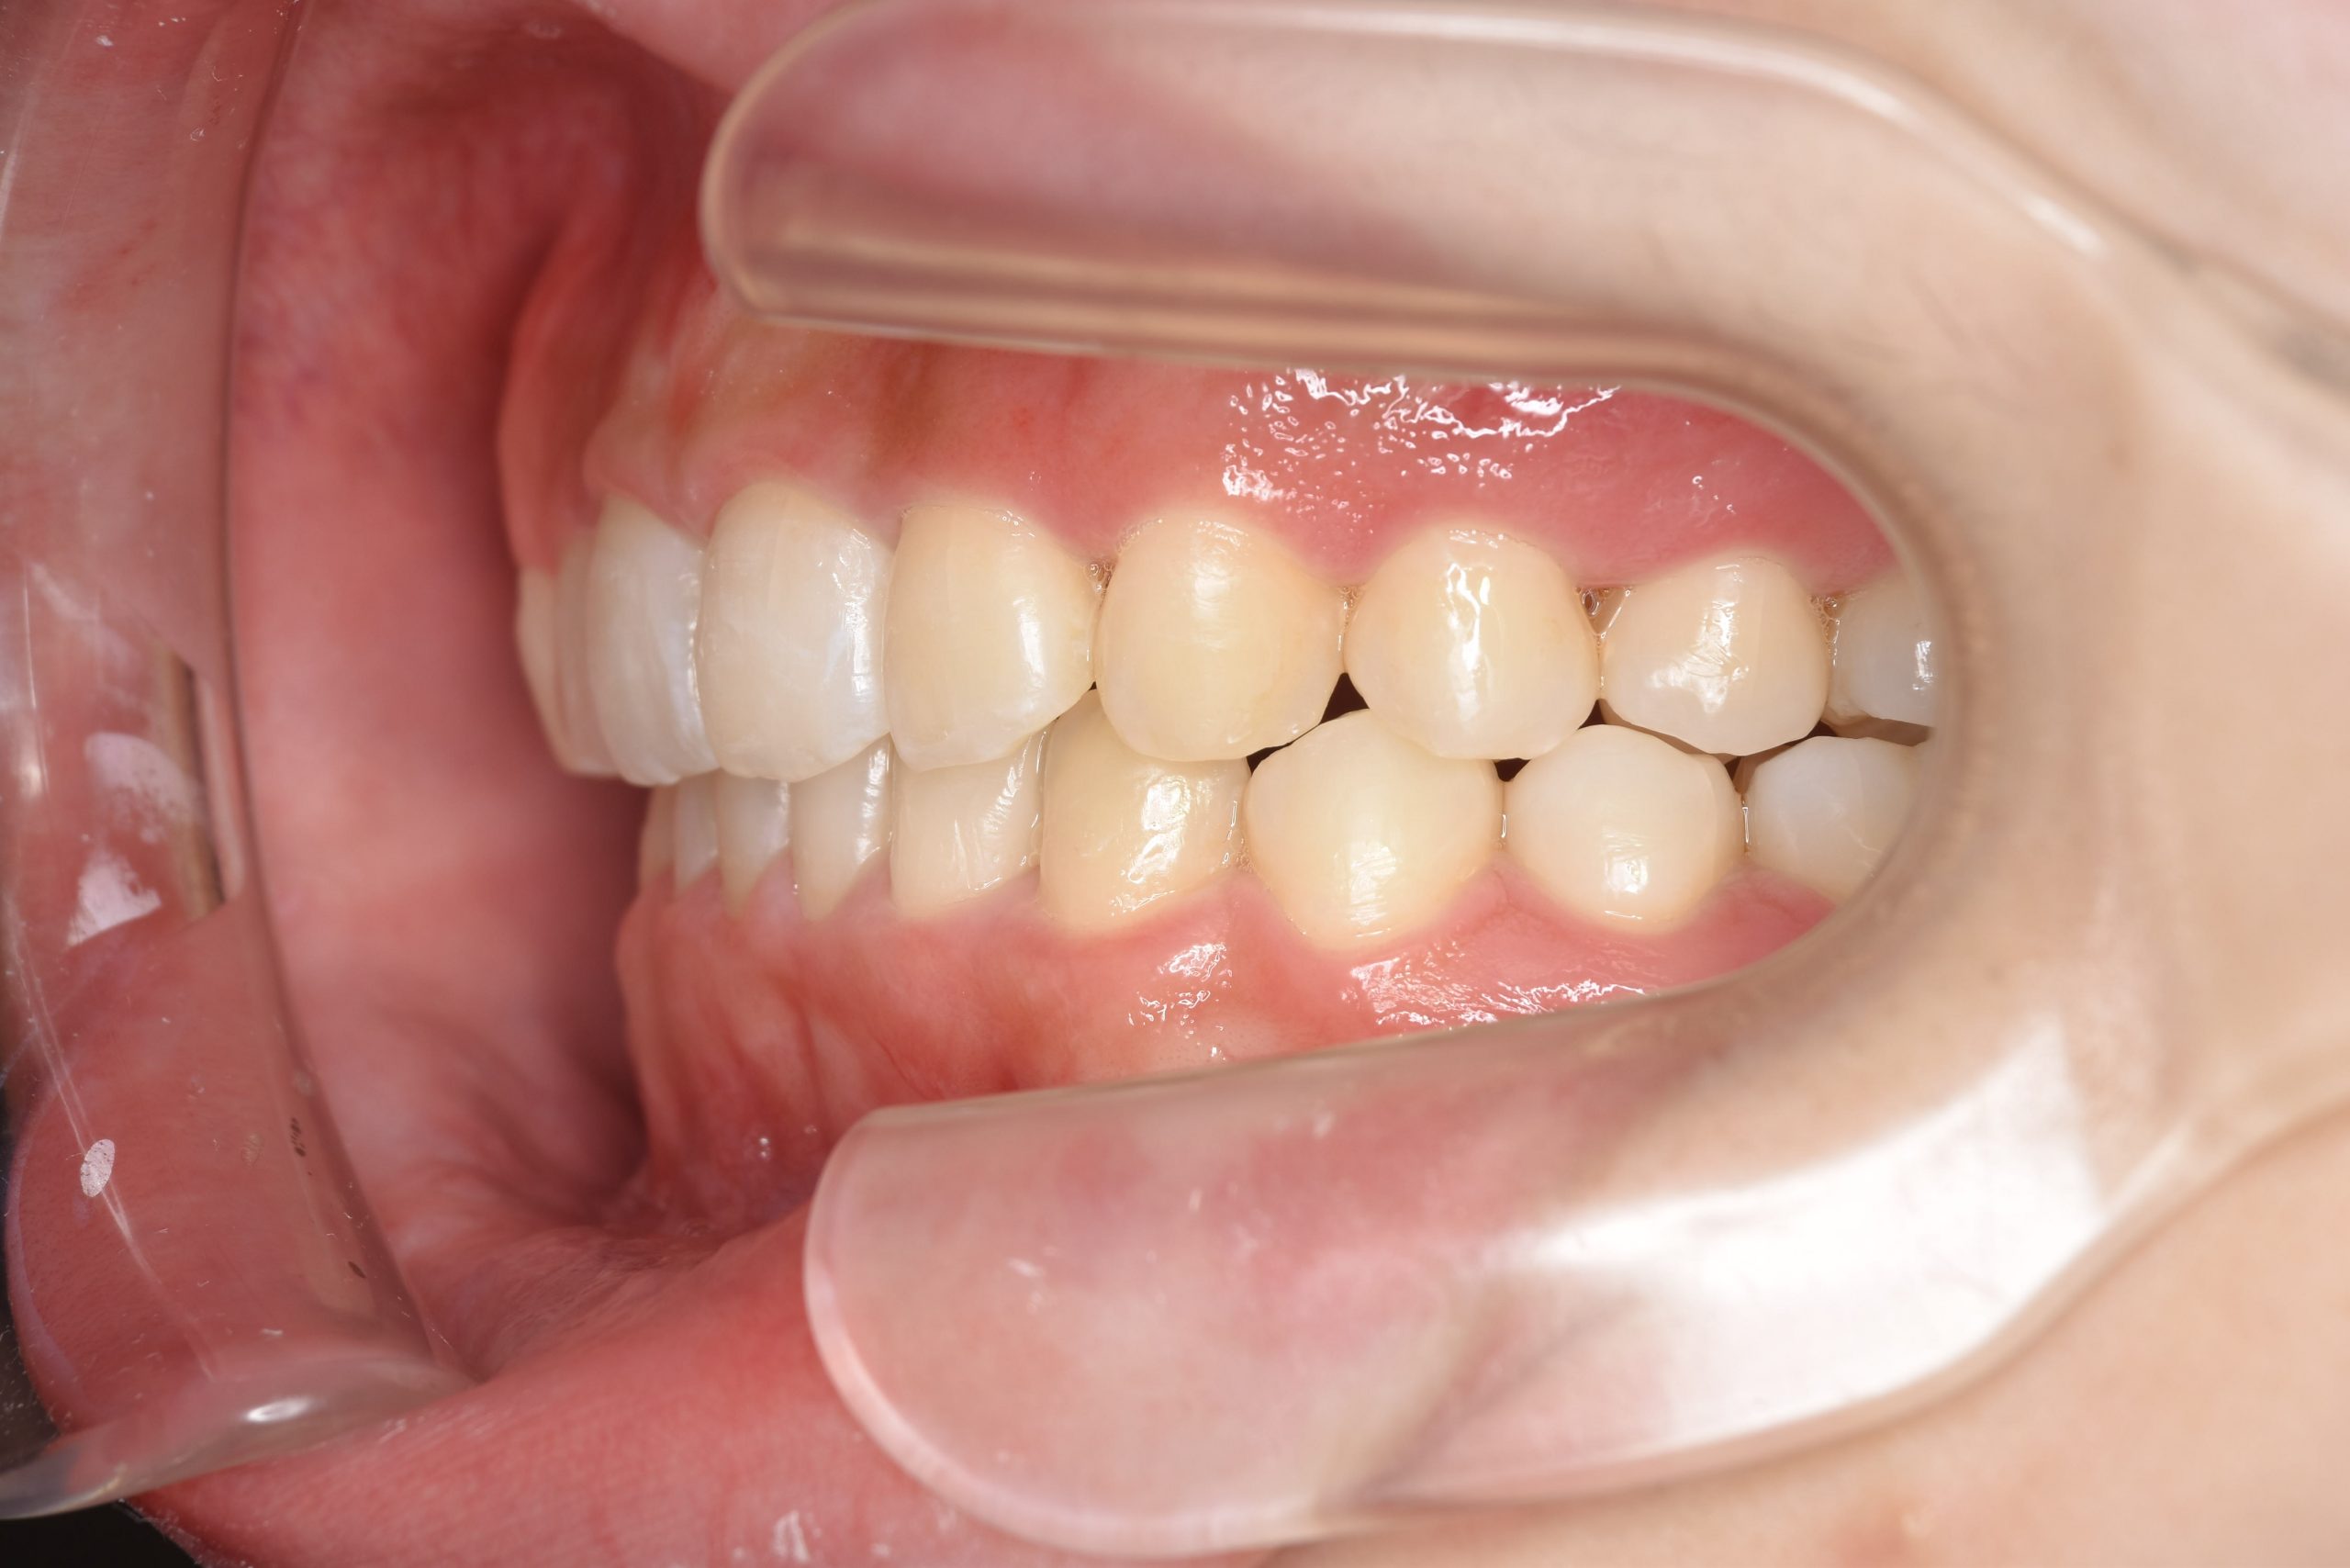

ビフォー

インビザライン矯正治療|症例_315

主訴 食べ物を前歯で噛み切れない|上顎の右側の歯が重なっている|下の歯がガタガタ

施術内容 MSEと下顎リンガルアーチを用いて上下顎骨を拡大した。

その後アライナー型矯正装置(インビザライン)を用いて非抜歯で歯牙を配列した。

口元の突出感、鼻閉症状、鼾は改善された。

治癒期間 1年6ヶ月間